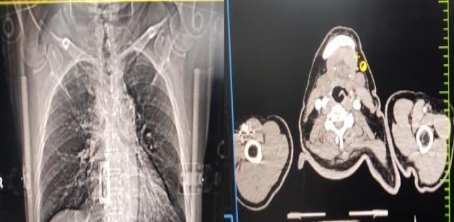

张先生(化名)今年77岁,确诊肺恶性肿瘤伴转移,近一月以来诉胸闷、痰中带血,入院后突发剧烈咳嗽,伴咯鲜血。CT检查结果显示为邻近支气管继发瘤体侵犯破裂出血,导致急性大咯血。经抢救,在止血药和缩血管药物的治疗下,张先生生命体征得以稳定,但仍有活动性出血。

情况紧急,肿瘤中心经过认真分析及评估患者病情后,及时进行介入栓塞止血急诊手术。经过多学科协作,术中通过造影顺利地找到了出血的动脉,将微导管插入出血的支气管动脉进行了栓塞,手术不到1小时顺利完成。术后止血效果立竿见影,患者在不使用止血药和缩血管药物的情况下,再没有出现咯血的表现。